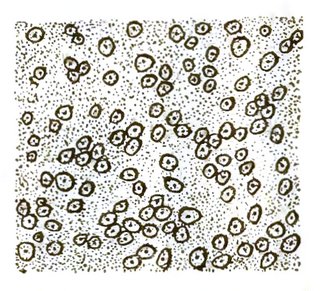

| XLIV. Normal spleen and spleen affected by Texas fever | 504 |

| XLV. Texas fever | 504 |